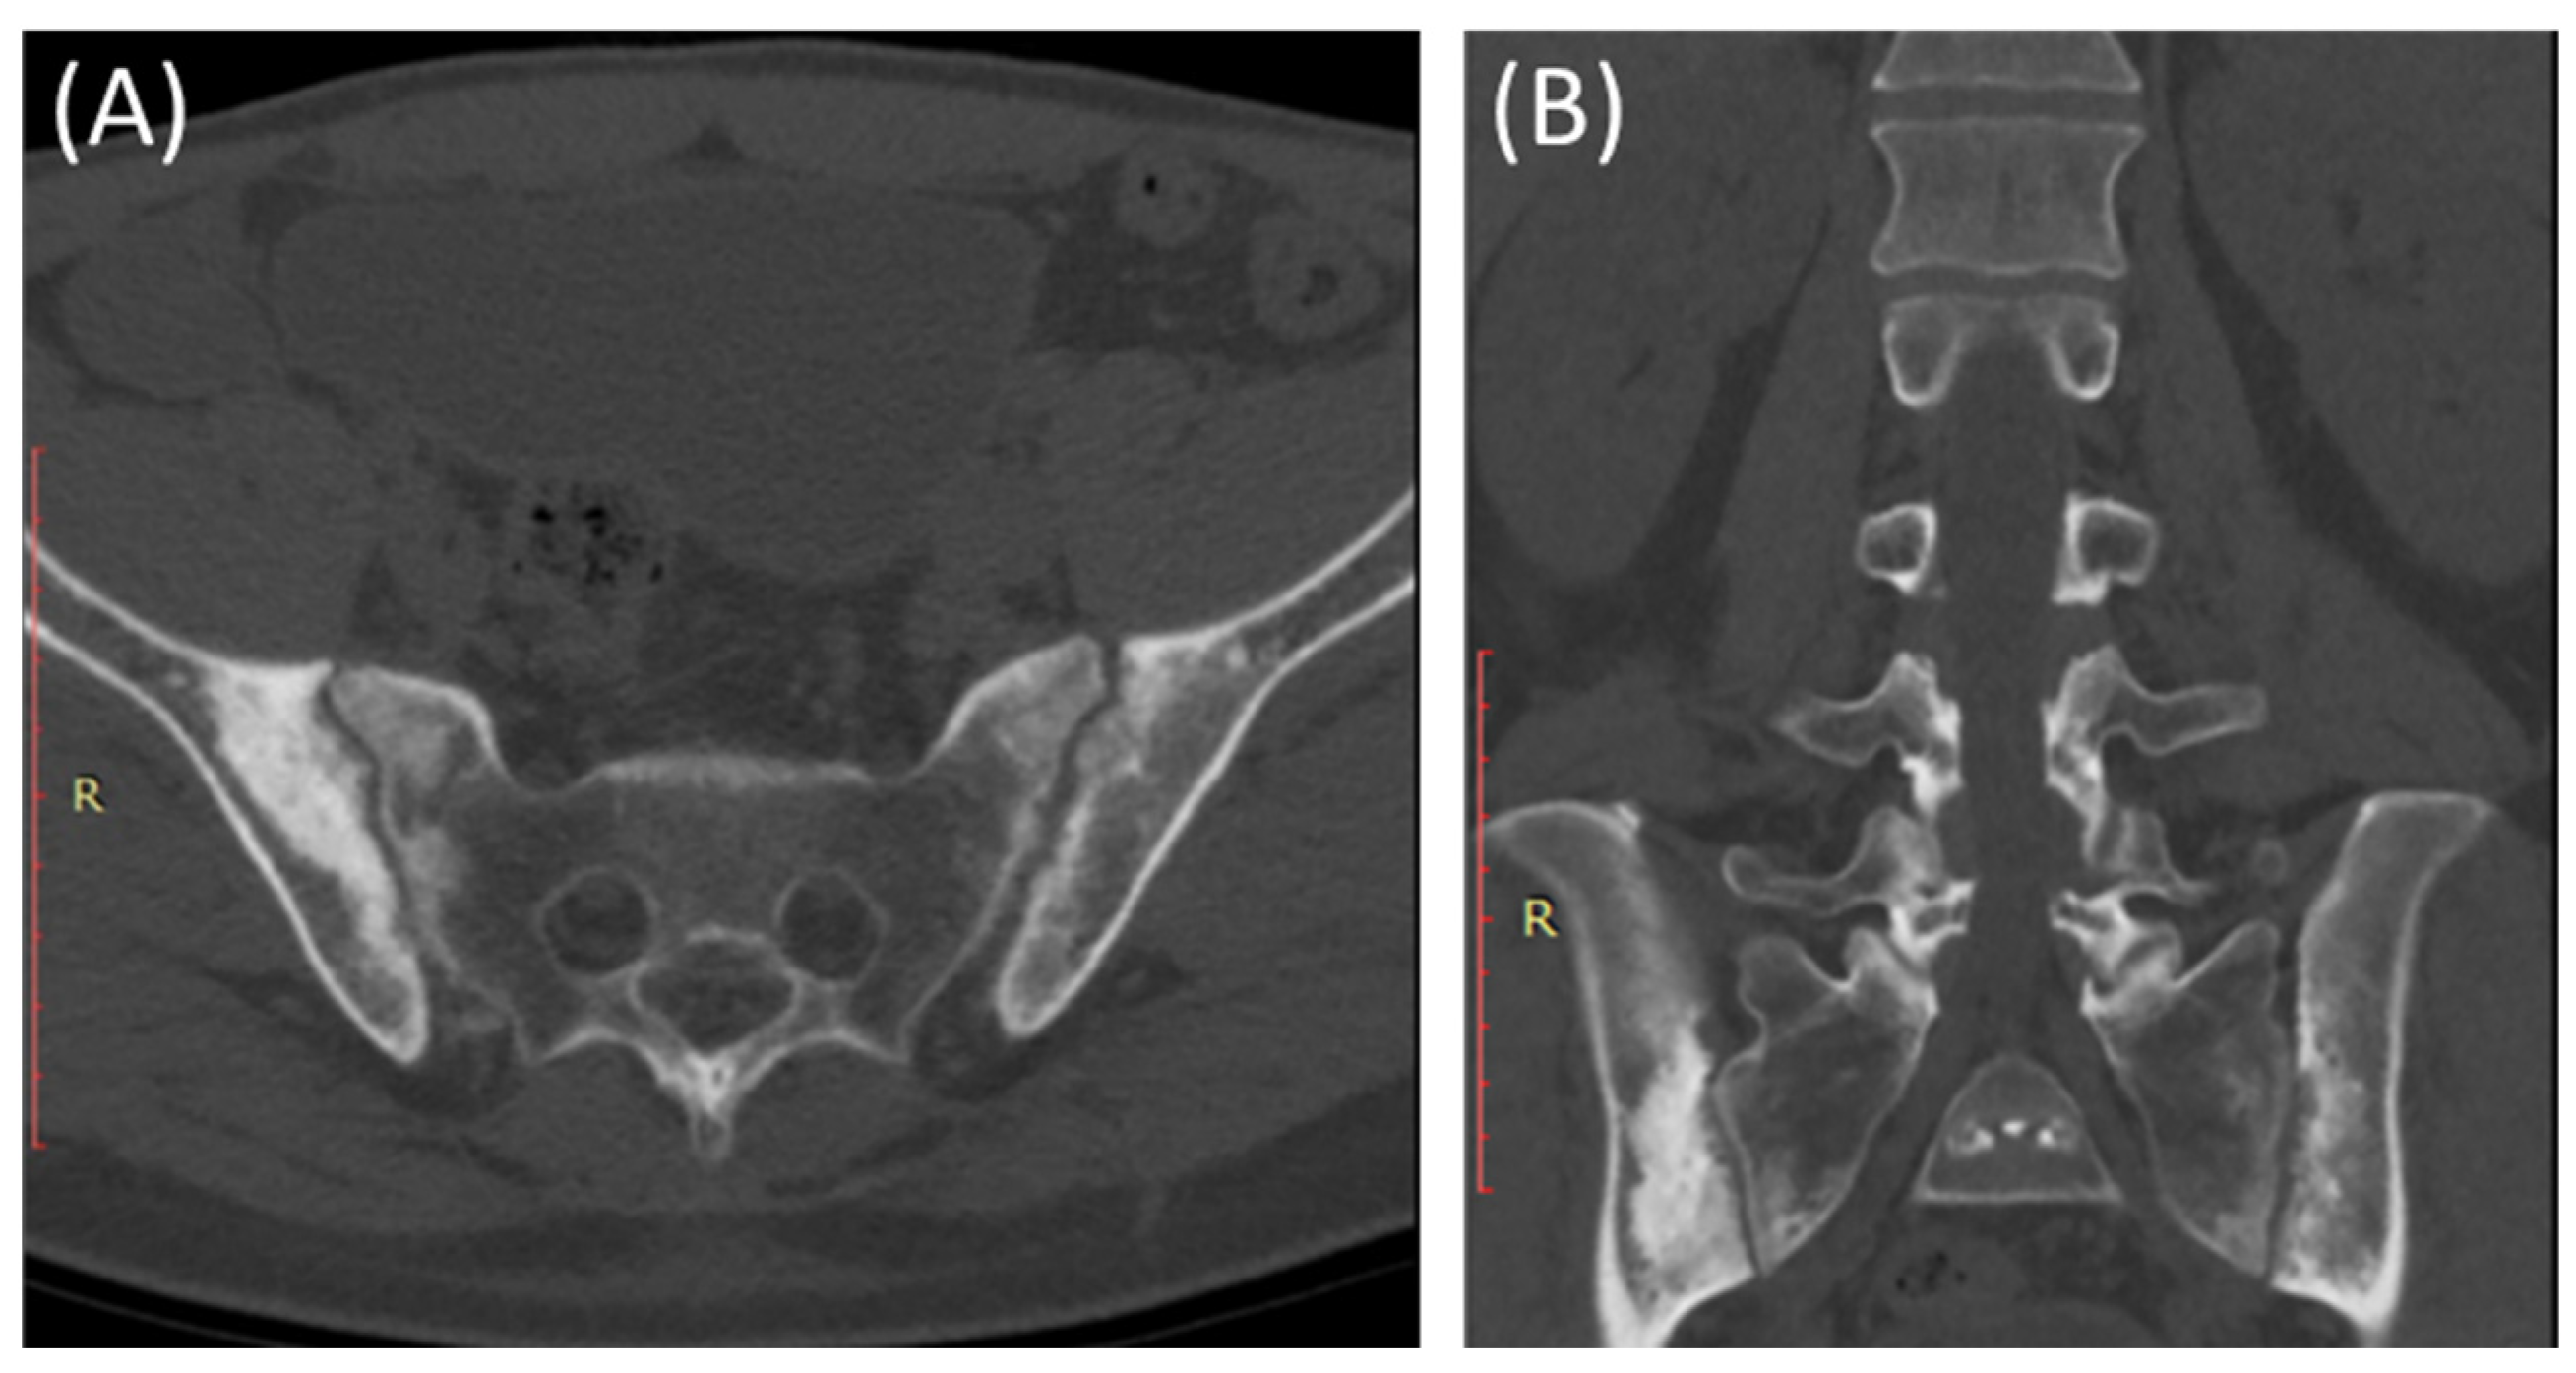

CT scans provide more detailed images of the sacroiliac joint and can reveal erosions, sclerosis, and joint space narrowing with greater clarity than X-rays [13]. Severe sacroiliitis, particularly in cases of ankylosing spondylitis, can lead to complete fusion or ankylosis of the sacroiliac joint [4]. CT scans can demonstrate the fusion as a solid, bony bridge between the sacrum and ilium [4]. CT scans can also assess soft tissues surrounding the SIJ, such as ligaments, tendons, and muscles, which may be inflamed in cases of sacroiliitis [44] as demonstrated in Figure 4 and Figure 5.

Figure 4.

Axial bone window CT scan (A) and coronal bone window CT scan (B) for a 41-year-old male presenting with Rt sciatica suggestive of bilateral sacroiliitis (same Patient as in Figure 3).

Figure 5.

Axial bone window CT scan (A) showing Chronic sacroiliitis with ankyloses of the sacroiliac and a sagittal bone window CT scan (B) showing Syndesmophytes in the spine in a 55-year-old patient with Ankylosing spondylitis.

CT scans can provide detailed information about adjacent structures, such as the lumbar spine, hip joints, and pelvic bones, to evaluate for any associated abnormalities or complications [48].